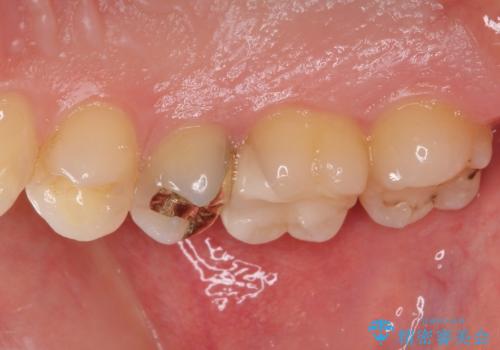

- 奥歯の銀歯の下にあるむし歯治療を希望して来院された患者様です。

口を開けたときに見えてしまう部分はセラミックインレーやジルコニアクラウンに、目立たない部分はゴールドインレーにてむし歯治療を行うこととしました。

機能面を優先すると、PGAインレー(ゴールドインレー)による修復治療やPGAクラウンによる補綴治療が望ましいのですが、笑ったときに見えている銀歯がどうしても気なってしまうとのことで、目立ってしまう奥歯はセラミックインレーやセラミッククラウンを装着することとしました。

見た目を気にすることなくむし歯治療を行うことができ、患者様に大変満足していただきました。